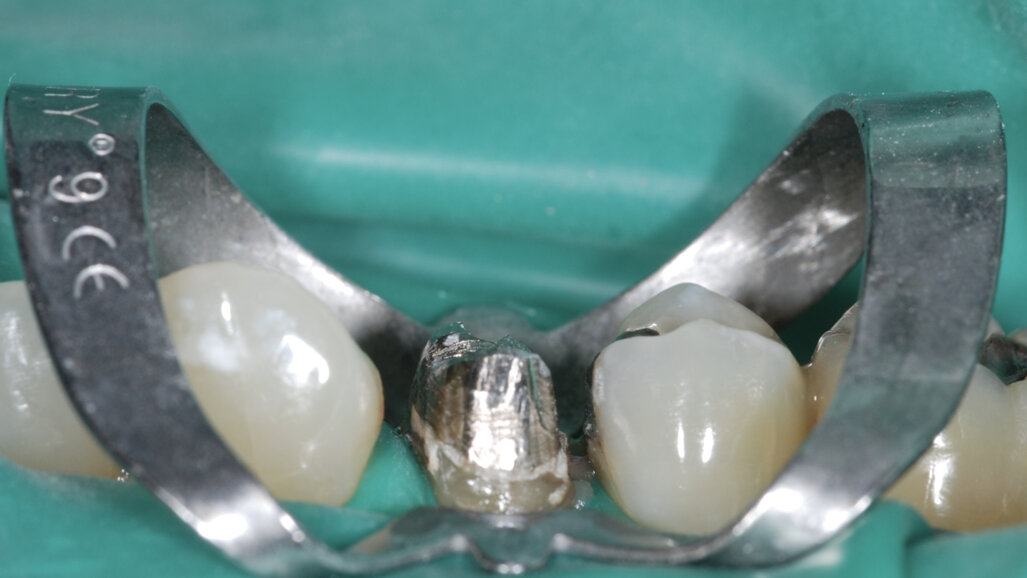

Il est important d’informer les patients de cette possibilité de sauver leurs dents même gravement endommagées et du pronostic du traitement par rapport à un implant. Bien que les implants soient très fiables, ils ne sont pas sans risque de complications. Lorsqu’ils sont bien informés, les patients choisissent souvent de conserver leurs dents naturelles.7 Aujourd’hui, les meilleures connaissances cliniques, la disponibilité de matériaux biocéramiques pour la réparation des lésions d’origine iatrogène et des défauts anatomiques, ainsi que l’utilisation généralisée du microscope opératoire, ont considérablement amélioré la prédictibilité de ces traitements.8, 9 Dès que la décision a été prise d’entreprendre le retraitement orthograde d’une dent et que toute restauration directe ou indirecte existante a été éliminée, la repréparation de la cavité d’accès est donc l’étape critique suivante. Il ne s’agit pas de créer un nouvel accès, mais plutôt de mieux délimiter l’accès existant afin d’optimiser l’entrée dans le système canalaire. Le champ opératoire doit être isolé à l’aide d’une digue en caoutchouc le plus tôt possible, de préférence immédiatement après le retrait de l’ancienne restauration. Notamment, toutes les procédures réalisées sous l’isolation d’une digue en caoutchouc sont associées à une production minimale de microgouttelettes salivaires.

Les restaurations directes ou indirectes (telles que les obturations, les couronnes, les bridges) doivent toujours être éliminées avant les procédures endodontiques, de façon à permettre une évaluation biomécanique de la structure dentaire encore présente et la pose d’un diagnostic précis pour la restauration. Leur retrait améliore également la visibilité et l’isolation et facilite le repérage des orifices canalaires. D’anciennes restaurations laissées en place augmentent notablement la probabilité d’échec en raison des difficultés qu’elles créent pour accéder au système canalaire et du risque de micro et macropercolations secondaires. La réalisation d’un retraitement à travers une restauration existante doit être limitée à des cas bien spécifiques, et toujours avec l’accord du patient.